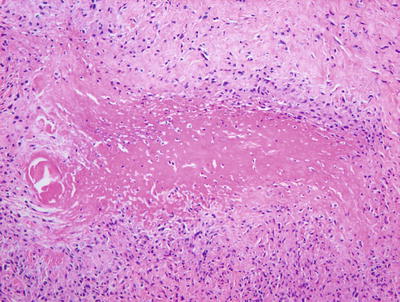

Necrobiosis lipoidica is uncommon in children as it is usually a late complication of long-standing diabetes mellitus [58]. However, rare cases have been described in children with long-standing diabetes. In these cases, the histology is indistinguishable from that seen in adult cases of necrobiosis lipodica. Within the reticular dermis, a palisade of histiocytes surrounds a large central area of pale staining necrobiotic collagen (Figs.6.18, 6.19 and 6.21). The histiocytes may have abundant cytoplasm and in well-developed lesions, lipid may be present within the cytoplasm. Multinucleated giant cells may be present. A superficial and deep peri-vascular infiltrate of lymphocytes, histiocytes and plasma cells is present. Similar clusters of hematopoietic cells aggregate into well-formed germinal centers may be present at the interface between the deep dermis and subcutaneous fat (Fig. 6.20). Dermal blood vessels demonstrate thickened walls and in some cases occluded vascular lumen.

Fig. 6.18

Low magnification demonstrates large foci of necrobiotic collagen surrounded by a rim of histiocytes giving a layered appearance in necrobiosis lipoidica

Fig. 6.19

Necrobiosis lipoidica frequently has lymphoid follicles in addition to the palisade of histiocytes